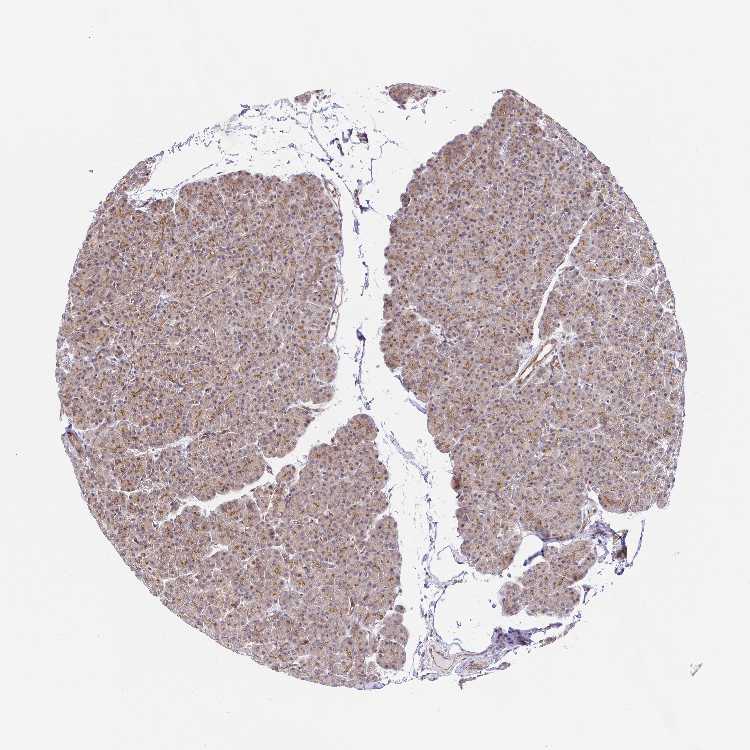

PANCREAS - Antibody stainingi

Antibody staining in the annotated cell types in the current human tissue is reported as not detected, low, medium, or high, based on conventional immunohistochemistry profiling in selected tissues. This score is based on the combination of the staining intensity and fraction of stained cells.

Each image is clickable and will lead to virtual microscopy that enables deeper exploration of all samples and also displays staining intensity scores, fraction scores and subcellular localization as well as patient and tissue information for each sample.

Antibody HPA038793Antibody HPA053691

Exocrine glandular cells MediumMedium

Pancreatic endocrine cells Not detectedNot detected